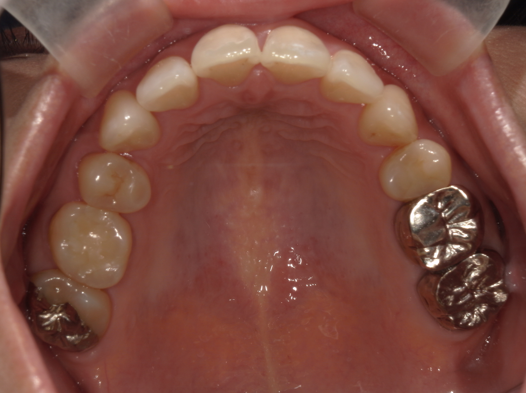

症例2:八重歯が気になる

| 患者様データ | 20代 女性 |

| 来院主訴 | 八重歯が気になる。 |

| 治療内容 | 八重歯を治すために上の親知らずを抜歯し、インビザラインにてマウスピース矯正を開始しました。かみ合わせを整えるためにゴムかけを行いました。 |

| 概算治療費 | 約85万円 |

| 治療期間 | 1年3ヶ月 |

| 通院回数 | 8回 |